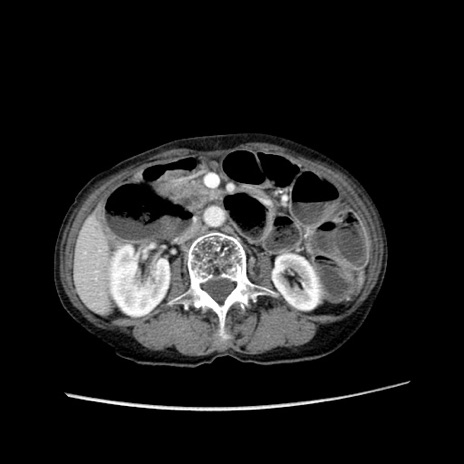

症例25(横断像)

【症例】80歳代女性

【主訴】胸のつかえ感

【現病歴】約9時間前に食後から胸のつかえた感じあり、嘔吐あり、来院。

【既往歴】胃癌(全摘)、胆摘、虫垂炎

【身体所見】心窩部に圧痛あり、反跳痛なし。

【データ】WBC 5700、CRP 0.05